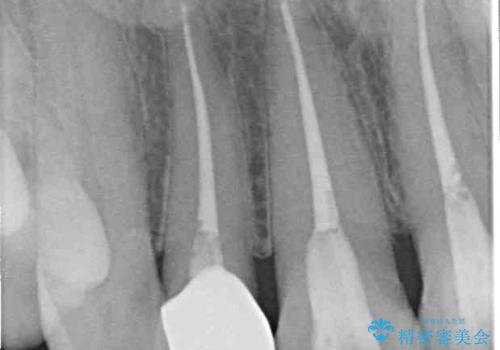

- 上顎4前歯に装着されているセラミッククラウンのうち、ひとつが欠けてしまったとのことで来院された患者様です。

土台となっている歯には問題がないため、周囲のセラミッククラウンと色調が合うように、オーダーメイドタイプのセラミッククラウンにて補綴治療を行うこととしました.

欠けてしまったセラミッククラウンはガラス系セラミッククラウンであったため、今回製作する歯は、強度の強いジルコニアセラミッククラウンとしました。

クラウンの種類は異なりますが、色調の適合したクラウンを装着することができました。